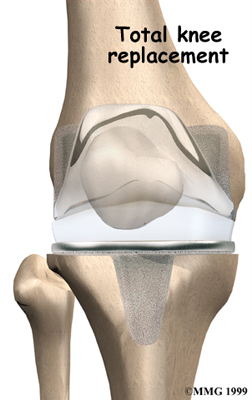

Artificial Knee Replacement

An artificial knee replacement is the ultimate solution for advanced knee OA.

Surgeons prefer not to put a new knee joint in patients younger than 60. This is because younger patients are generally more active and might put too much stress on the joint, causing it to loosen or even crack. A revision surgery to replace a damaged prosthesis is harder to do, has more possible complications, and is usually less successful than a first-time joint replacement surgery.

Related Document: FYZICAL Metairie's Guide to Artificial Joint Replacement of the Knee